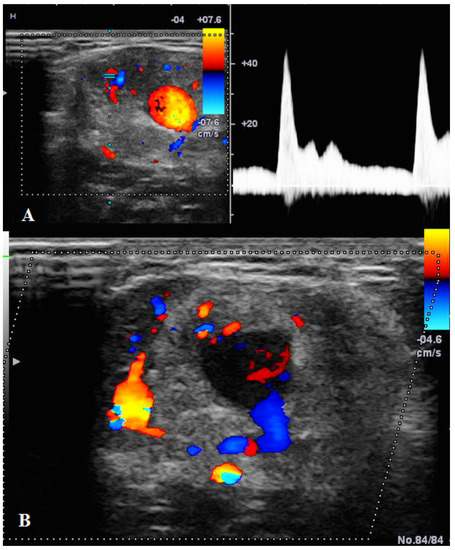

| Manole et al./2022 | US | First-line imaging tool |

| - detection and characterization | ||

| - assessment of the vessel | ||

| - follow-up | ||